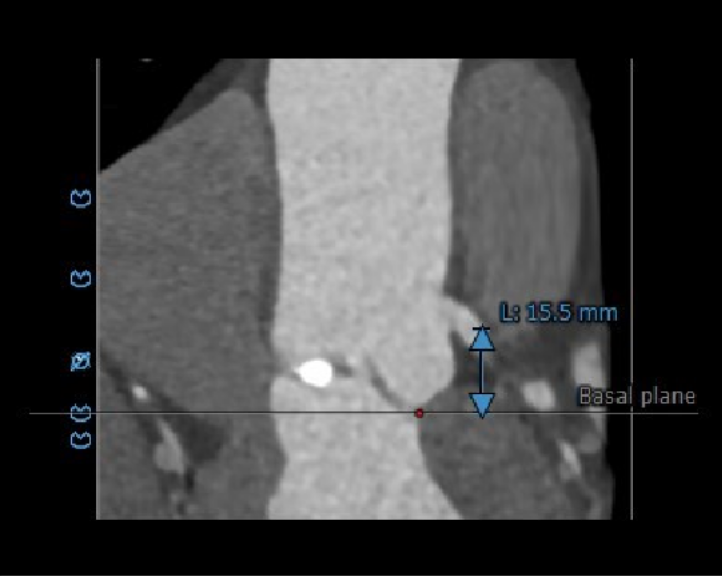

冠脉高度测量

左冠开口高度15.5mm

右冠开口高度20.0mm